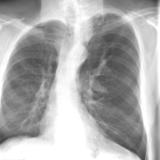

Hypoplastic right lung

Date: 08/15/2012

Views: 3141